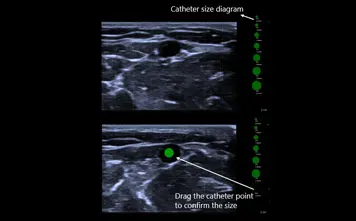

VA Grid

Vascular Access Grid - грид за съдов достъп е удобен инструмент за сравнение на диаметъра на съдовете и размерите на катетрите на различни фокус места, което улеснява избора на подходящия размер катетър.

- Линиите на грида се променят според дълбочината.

- Диаграма за размер на катетъра, която интуитивно показва диаметъра на катетъра.

- Помага за ефективен избор на размер на катетъра, намалявайки риска от тромбоза.